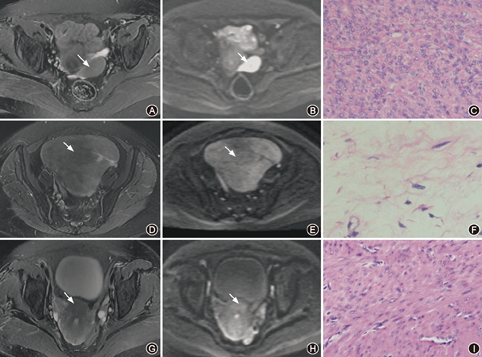

17例富细胞性肌瘤在DWI呈高或稍高信号;4例变性肌瘤在DWI呈高或稍高信号,2例呈等信号,4例呈稍低或低信号;5例普通未变性肌瘤呈高或稍高信号,19例呈等信号,9例呈稍低或低信号(表2,图1)。

富细胞性组肌瘤ADC值为(1.01±0.14)×10-3 mm2/s;变性组肌瘤ADC值为(1.73±0.49)×10-3 mm2/s,其中水肿、囊变,玻璃样变,出血坏死型肌瘤ADC值分别为(2.15±0.35)×10-3 mm2/s、(1.53±0.39)×10-3 mm2/s和(1.28±0.15)×10-3 mm2/s;普通未变性组肌瘤ADC值为(1.38±0.22)×10-3 mm2/s。邻近正常子宫肌层(对照组)的ADC值为(1.35±0.16 )×10-3 mm2/s (图2)。富细胞性、变性、普通未变性组肌瘤及对照组的ADC值均符合正态分布,该四组间比较差异有统计学意义(F=21.172,P<0.05),普通未变性组肌瘤与对照组的ADC值差异无统计学意义(P=0.623),余组间两两比较差异均有统计学意义(均P<0.05)。诊断富细胞性肌瘤的ROC曲线下面积为0.950,最佳鉴别阈值为1.11×10-3 mm2/s,敏感度与特异度分别为88.2%和93.0%。

本研究中富细胞性肌瘤在DWI上多呈高信号,变性组肌瘤可呈低、等、高信号,普通未变性肌瘤则多呈等信号。提示当常规序列难以鉴别子宫肌瘤病理类型时,若DWI为高信号,则富细胞性肌瘤可能;若信号较低则肌瘤变性可能。表明DWI序列在一定程度上反映了病变的病理组织学特征,对病灶的定性诊断有较大的帮助。本研究中2例变性肌瘤及2例普通未变性肌瘤在DWI亦为高信号,其ADC值未见明显减低,且病灶在T2WI序列上均呈稍高信号,考虑DWI高信号原因主要为T2透过效应的影响[13]。另1例DWI高信号的普通未变性肌瘤,ADC值减低,在T2WI序列上呈稍高信号,与富细胞性肌瘤相似,考虑该肌瘤的病理改变介于富细胞及普通未变性型之间,细胞排列较紧密、丰富,但尚未达到病理诊断富细胞性的标准。因此,单凭DWI信号特征尚不能准确的对子宫肌瘤做出分型诊断。